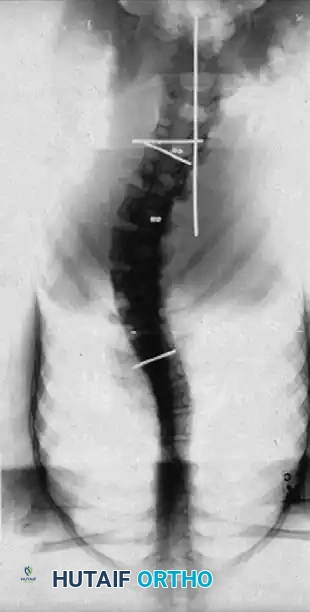

The biomechanical rationale for this procedure is rooted in the tension-band effect of the thoracic cage. In severe scoliosis, the ribs on the concave side of the curve become structurally contracted, acting as a rigid tether that resists coronal correction and derotation. Halsall et al. conducted pivotal cadaveric studies testing spinal flexibility before and after the sectioning of ribs on the tension (concave) side. Their findings demonstrated an average increase in coronal deflection of 53%, with the maximum increase in flexibility achieved when five or six apical ribs were resected or osteotomized.